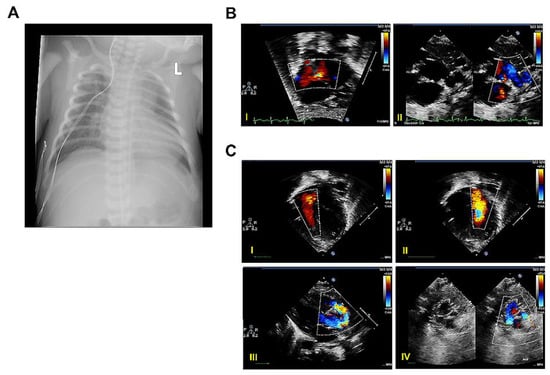

2.1.1. Case A

2.1.2. Case B